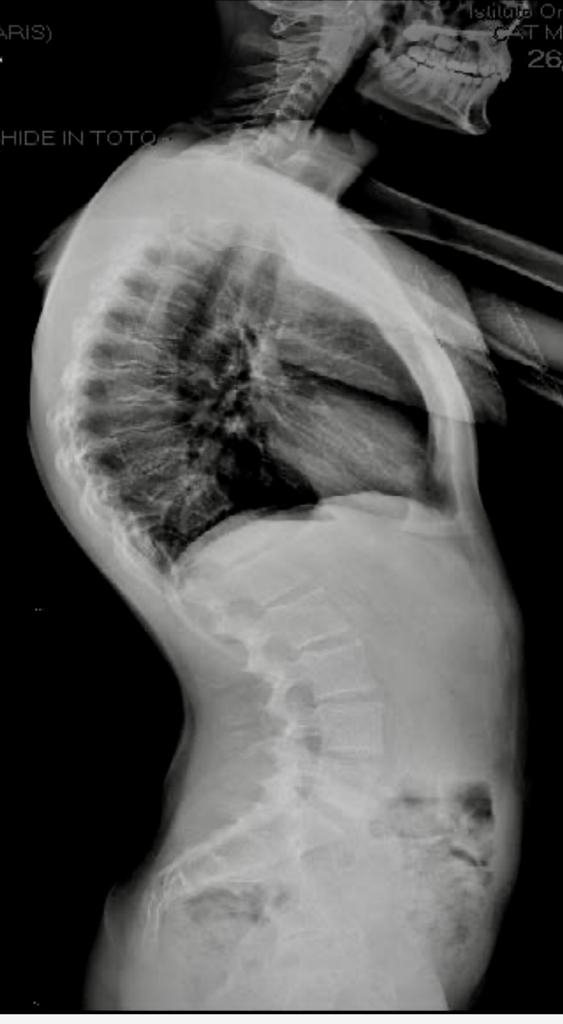

Ipercifosi: Quando la Curva Diventa Eccessiva

L'ipercifosi è una condizione in cui la curvatura della colonna vertebrale nella regione toracica diventa eccessiva, portando ad una postura arcuata e chiusa in avanti. Questa condizione può causare dolore alla schiena, tensione muscolare e limitazioni nella mobilità. In questi casi il trattamento riabilitativo diventa necessario.

Cifosi di Scheuermann: Quando la Curvatura Diventa Patologica

La cifosi di Scheuermann prende il nome dal medico danese Holger Scheuermann, che per primo la descrisse nel 1920. Questa condizione colpisce le vertebre toraciche superiori e si manifesta con una curva eccessiva della colonna vertebrale verso l'esterno. Si pensa che la cifosi di Scheuermann sia causata da un'anomalia nell’accrescimento delle cartilagini vertebrali durante l'adolescenza, che porta da una deformazione “a cuneo “ anteriore, con conseguente curvatura e deformità della colonna. Anche in questo caso il trattamento riabilitativo diventa necessario per proteggere la crescita ossea, e può essere associato al trattamento ortopedico con corsetto.